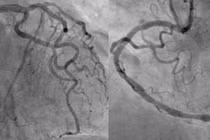

Trung tâm Tim mạch, Bệnh viện Hữu nghị Đa khoa Nghệ An vừa kịp thời can thiệp, cứu sống bệnh nhân người nước ngoài bị nhồi máu cơ tim cấp.